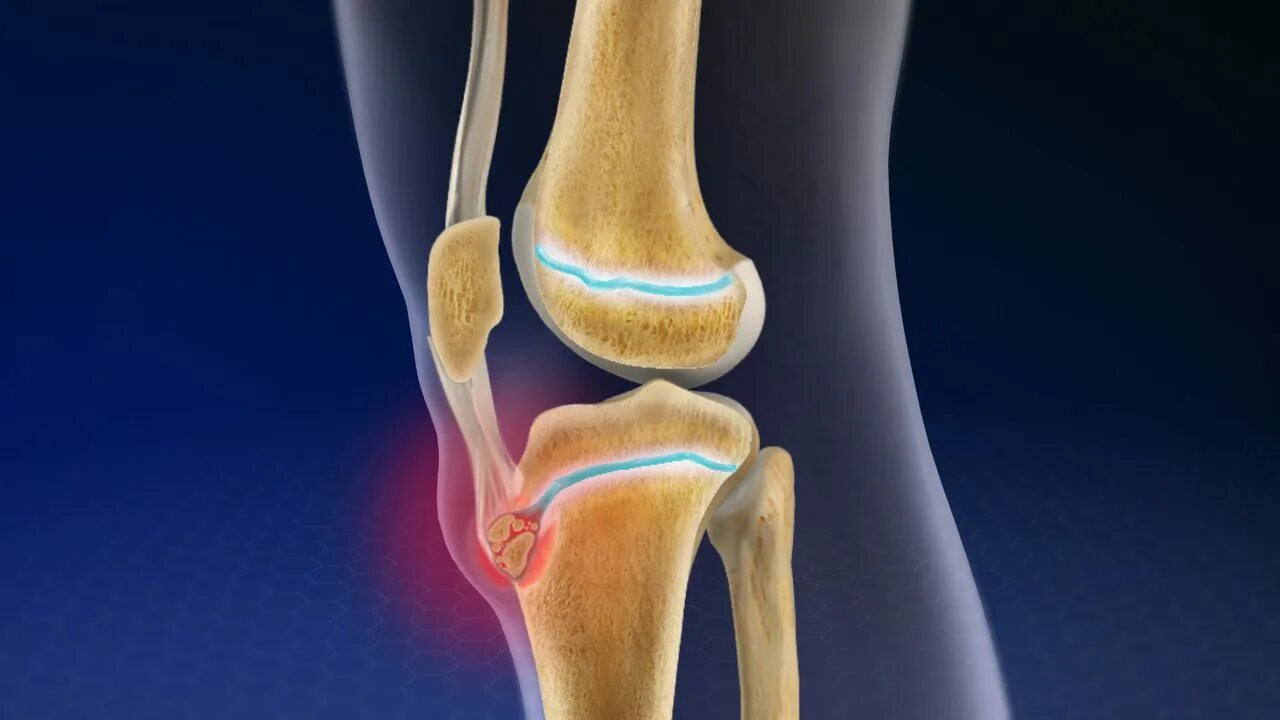

Болезнь осгут шляттера